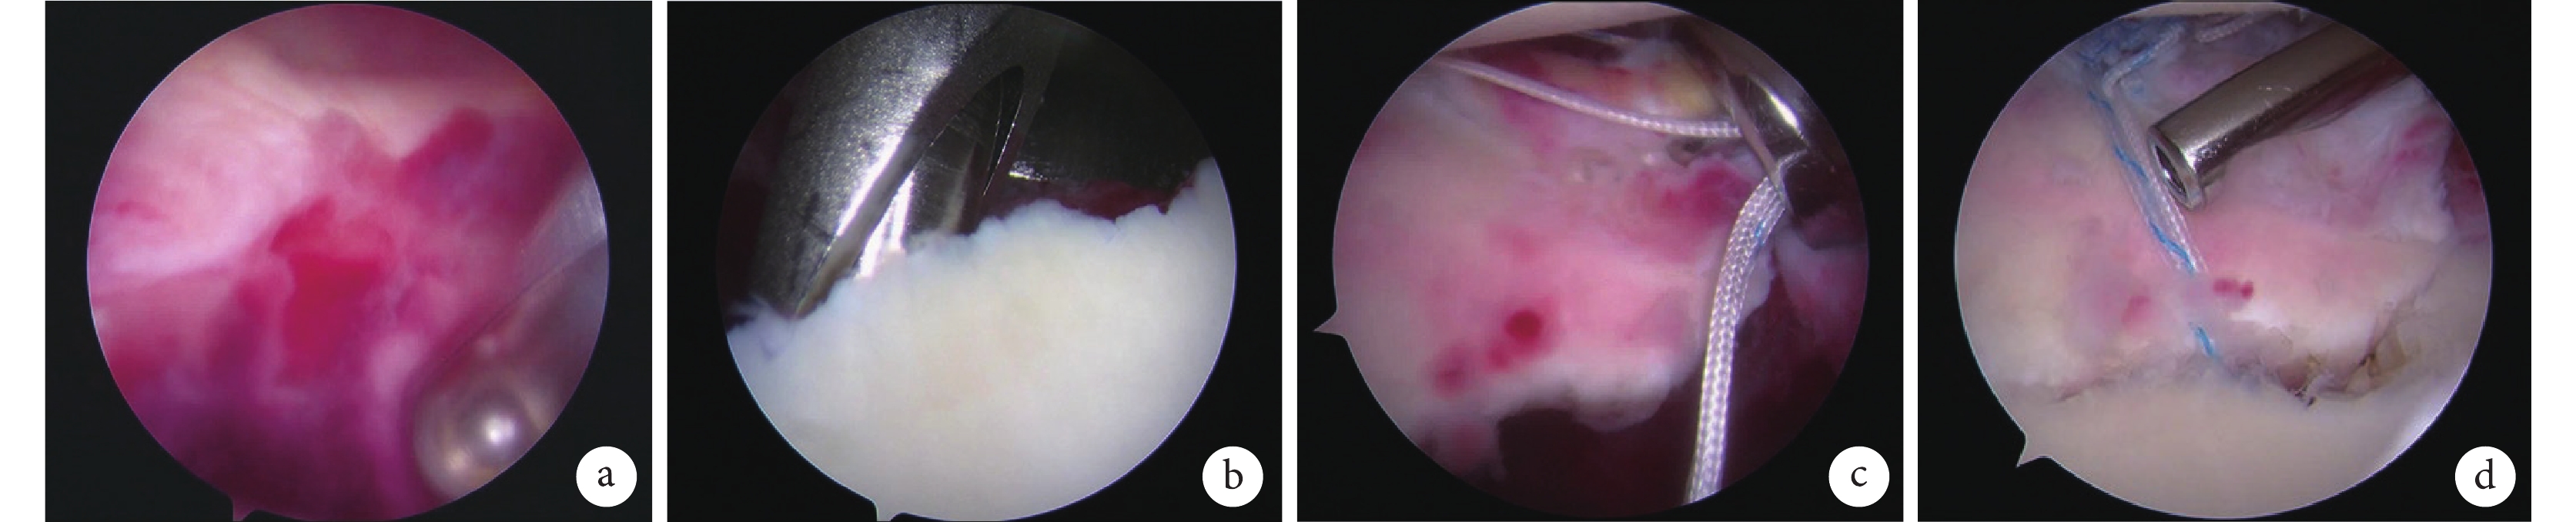

于肩關節盂骨折線內側上緣植入1枚帶線錨釘,位于骨折面上方且尾端不得突出于骨折面。于骨折塊前方盂肱下韌帶復合體內植入2根 PDS線,可通過牽拉此線明確骨折塊復位情況。用2根PDS線分別將帶線錨釘的雙股線經前方穿過盂肱下韌帶復合體貼骨折塊邊緣包繞骨折塊。此時用抓線器向上牽拉骨折塊解剖復位后打結固定。其中1根縫線采取三星結(SMC結)打結,即選一端尾線為柱線,另一端尾線為環繞線,兩端尾線同時收緊后再將環繞線繞柱線2次后穿過中間孔,此時拉動柱線即可滑動收緊線結復位骨折塊。該操作需注意以繞過骨折塊前方的尾線作為柱線,因撕脫骨折塊由于前方軟組織牽拉會有一定內翻,以前方尾線為柱線,在滑動收緊過程中可以糾正骨折塊內翻移位。線結收緊骨折塊復位后可繼續打結4~5次,防止SMC結滑脫。另1根縫線采用方結,進一步固定骨折塊。檢查骨折塊解剖復位、縫線固定牢固、骨折塊穩定性好,關閉切口。見圖1。

a. 清除血腫;b. 植入錨釘;c. 復位骨折塊并打結固定;d. 檢查固定

Figure1. Schematic diagram of surgical operationa. Removal of the hematoma; b. Inserted the anchor; c. Reduction and knot fixation of fracture; d. Examined the firmness of fracture